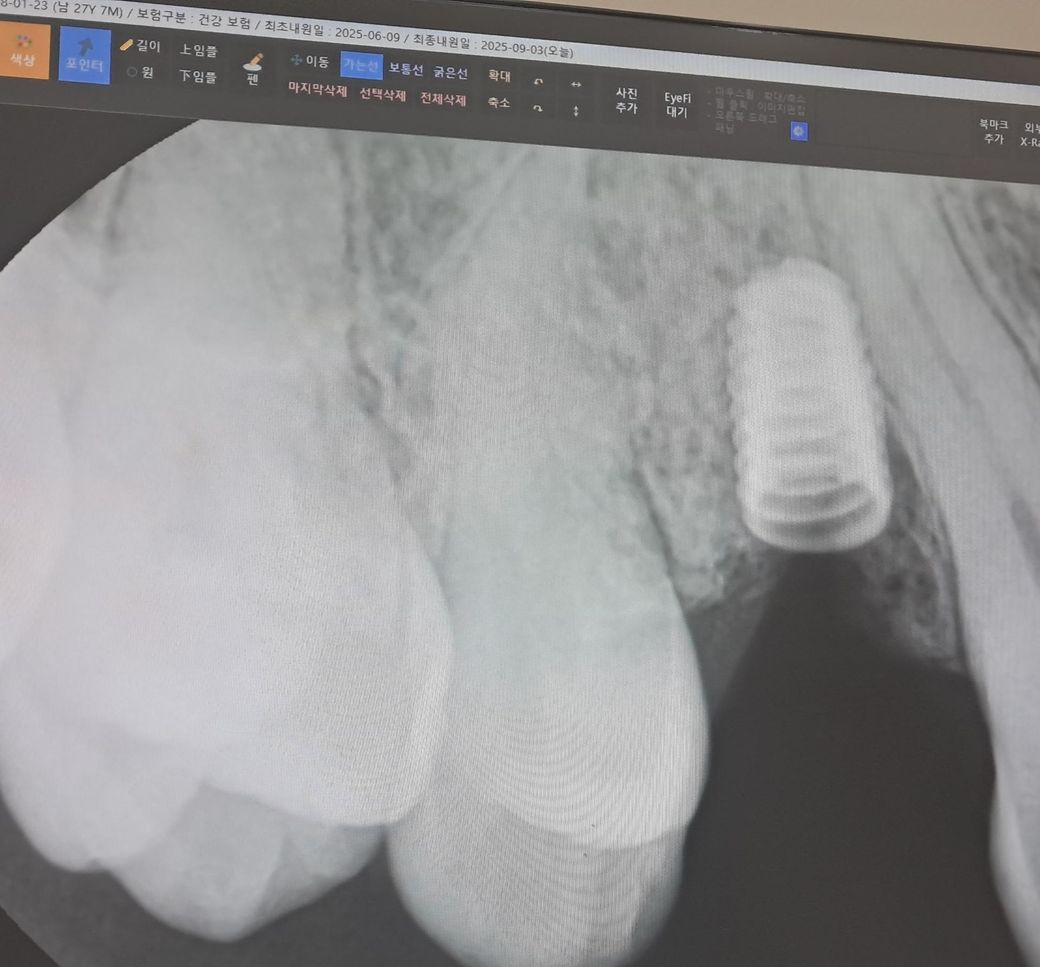

임플란트했던 치아 관련해서 질문드립니다.

임플란트를 한지는 6년이 지났고 평소에도 자주 음식물이 끼었습니다. 이번에는 그 치아가 흔들려서 치과에 내원하게 됐는데 뼈가 녹았다고 말씀해주셨습니다.

• 1번 째 사진

• 2번 째 사진

상황상 임플란트 주위염이 발생한 것 같습니다

다시 임플란트 머리 부위 나사 조이는걸로는 처치가 불완전하고 임플란트 뿌리(픽스쳐)를 빼고 다시 수술해야 합니다